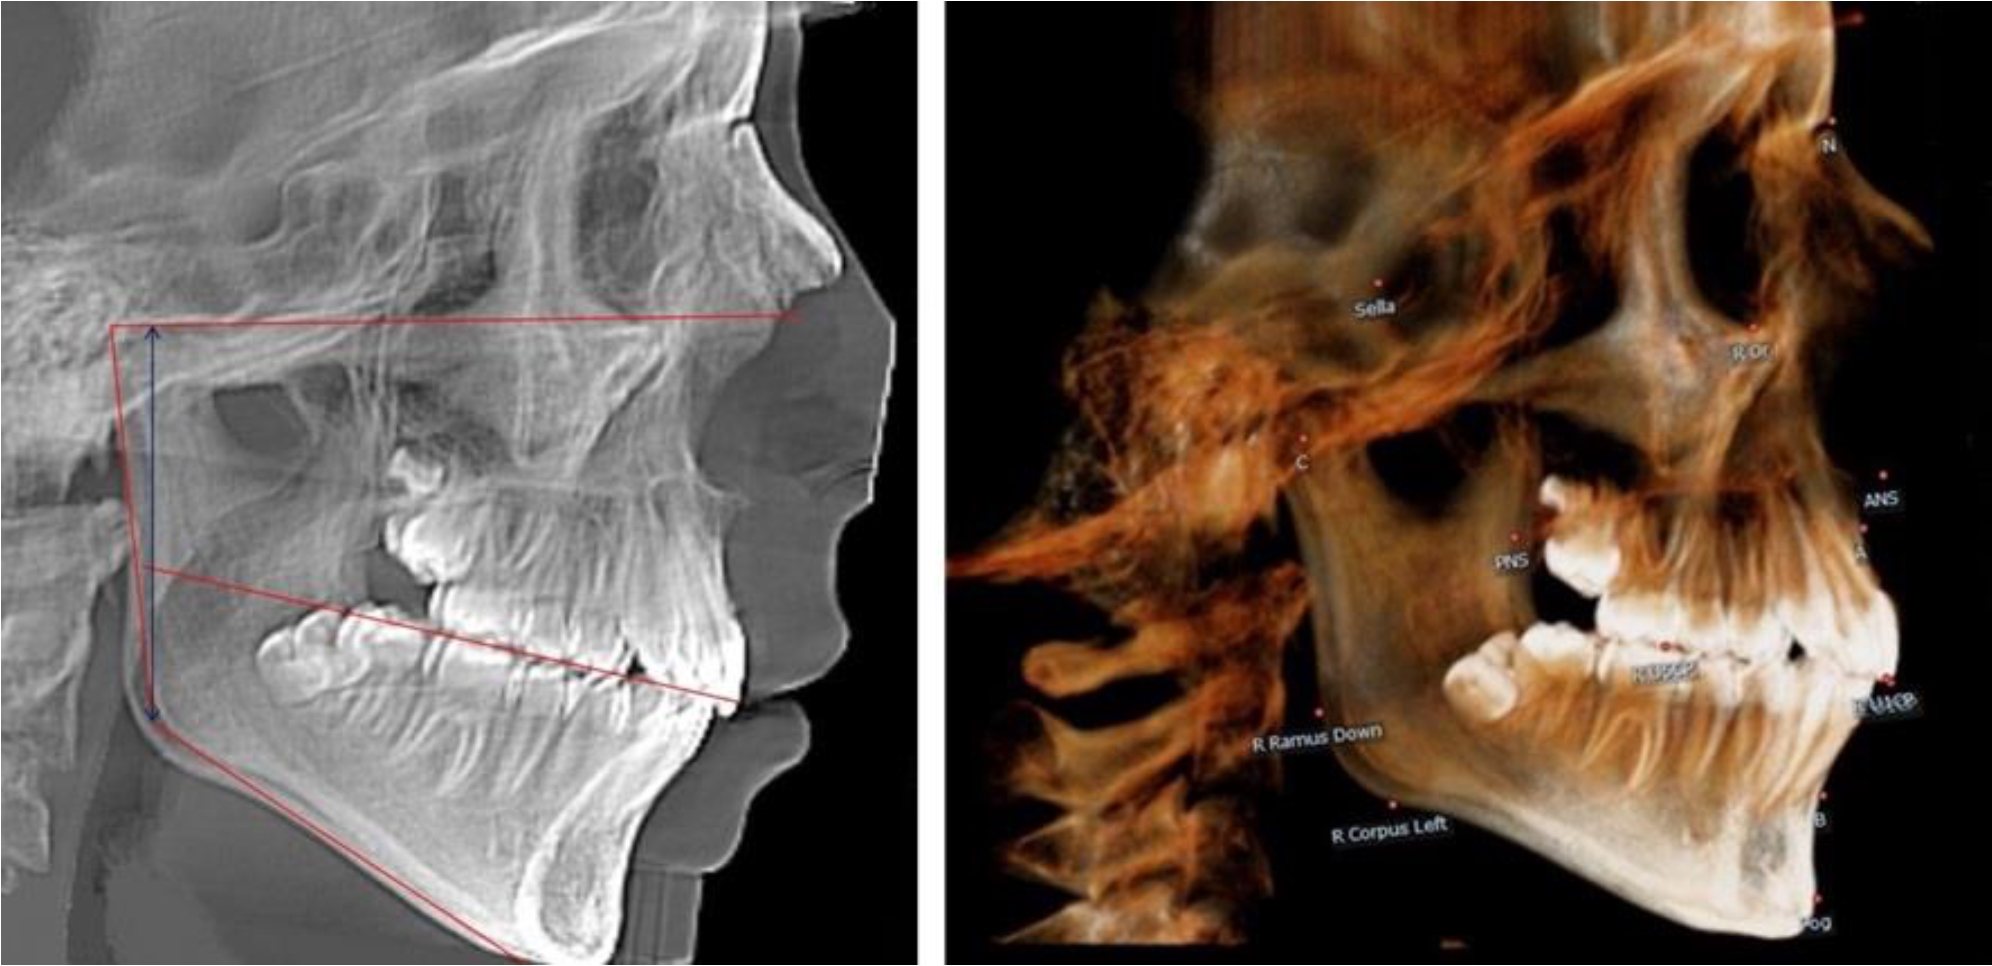

В 3-й группе были проанализированы 9 телерентгенограмм и 9 ортопантомограмм, что составило (8,49 ± 2,71) % от числа изученных рентгенограмм (рис. 3).

Рис. 3. ТРГ и ОПТГ пациента после смены молочных резцов

На всех рентгенограммах произошла смена молочных резцов постоянными. Окклюзионная линия делила ветвь на два отдела.

Высота ветви у детей у детей 3-й группы составляла (51,07 ± 2,72) мм, что было достоверно больше, чем у детей 1-й группы (р ˂ 0,05). При этом высота верхней окклюзионно-суставной части была (29,06 ± 1,44) мм, а нижней – (22,01 ± 1,59) мм. Высота верхней части была больше нижней, что и определяло особенности соразмерности частей ветви нижней челюсти в анализируемый возрастной период.

Относительные показатели соразмерности частей ветви нижней челюсти показали, что отношение высоты верхней части ветви к нижней в среднем составляло 1,32 ± 0,14. Отношение общей высоты ветви к верхней ее части составляло 1,75 ± 0,12, а отношение общей высоты ветви к нижней ее части было 2,32 ± 0,17, что и определяло особенности соразмерности частей ветви нижней челюсти в анализируемый возрастной период.

Рис. 4. ТРГ пациента после смены всех молочных резцов

Высота ветви у детей 4-й группы составляла (54,27 ± 2,59) мм, что было достоверно больше, чем у детей 1-й группы (р ˂ 0,05). При этом высота верхней окклюзионно-суставной части была (32,51 ± 1,72) мм, а нижней – (21,76 ± 1,42) мм. Высота верхней части была больше нижней, что и определяло особенности соразмерности частей ветви нижней челюсти в анализируемый возрастной период.

Относительные показатели соразмерности частей ветви нижней челюсти показали, что отношение высоты верхней части ветви к нижней в среднем составляло 1,49 ± 0,12. Отношение общей высоты ветви к верхней ее части составляло 1,67 ± 0,14, а отношение общей высоты ветви к нижней ее части было 2,49 ± 0,15, что и определяло особенности соразмерности частей ветви нижней челюсти в анализируемый возрастной период.